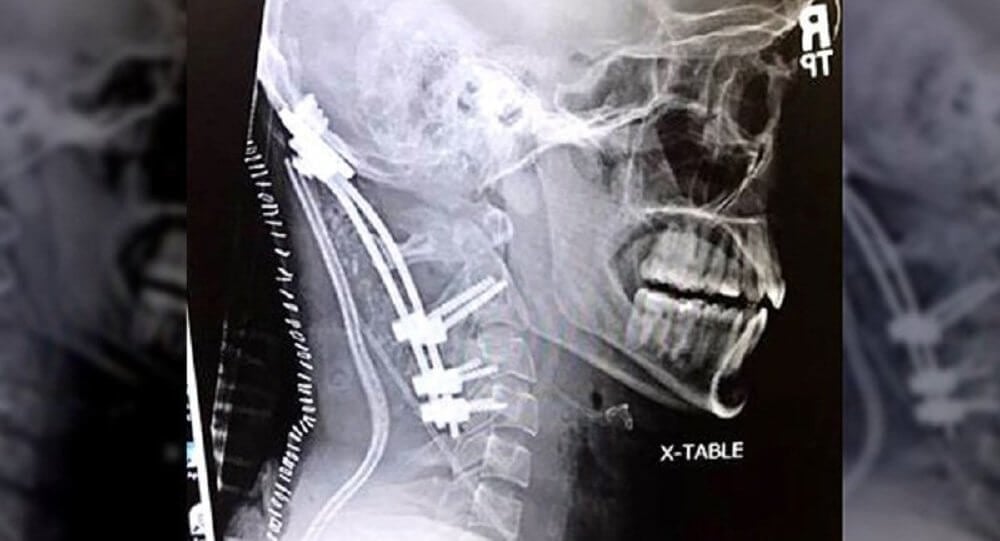

У Делайн обнаружили разрыв и дислокацию атланто-затылочного сочленения, соединяющего затылочную кость с первым шейным позвонком. «То, что она добралась до больницы живой, — это практически чудо, — говорит хирург Чарльз Гибсон. — В большинстве случаев с такой травмой умирают на месте происшествия».